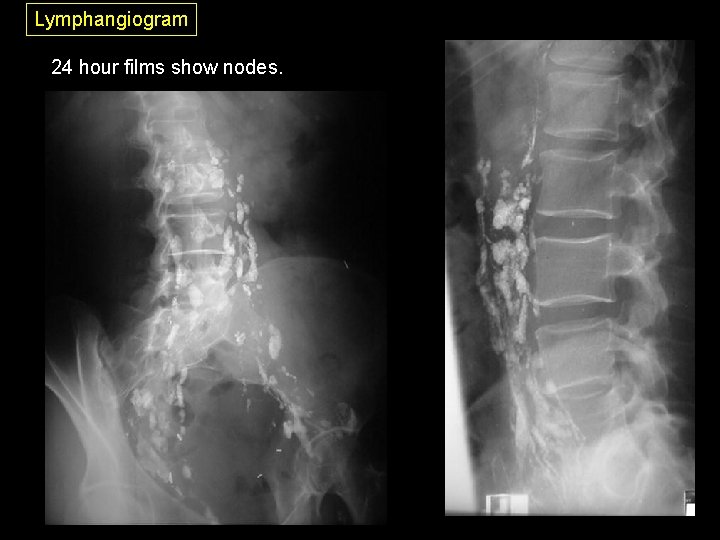

Lymphangiogram I Radiographic examination of the lymphatic system, primarily for lymphoma. 1. Inject blue dye between toes to localize lymph channels 2. Cut down to lymph vessel on dorsum of foot. 3. Contrast is injected slowly (45 minutes to an hour) due to the fragility of lymph vessels. Pediatric needles are used. 4. Films are taken the same day, though the contrast will not travel much further than the abdominal nodes. 5. The patient returns in 24 hours for a full set of films, abdominal and thoracic, in frontal, oblique, and lateral positions. First day films show mostly lymph channels.

Lymphangiogram 24 hour films show nodes.